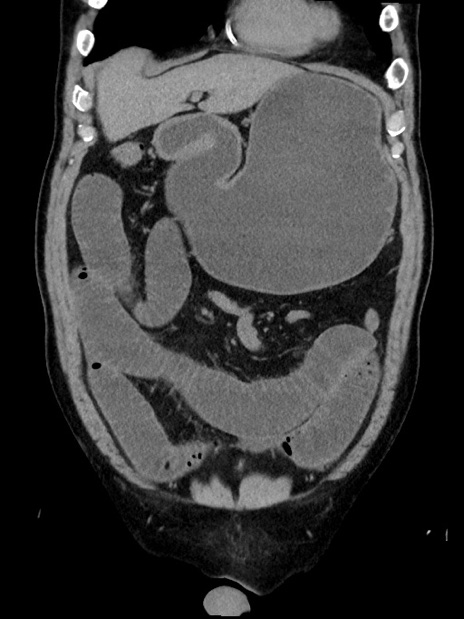

横断像

【症例】70歳代 男性

【主訴】腹部膨満、嘔吐

【現病歴】昨日より腹部膨満感出現。本日増悪し、仙痛出現。嘔吐あり、受診。

【既往歴】糖尿病、胆摘後

【身体所見】BP 149/80mmHg、HR 74/min、BT 35.9℃、腹部:膨満、軟、圧痛なし。腸雑音減弱あり。上腹部正中切開瘢痕あり。

【データ】WBC 13500、CRP 1.72